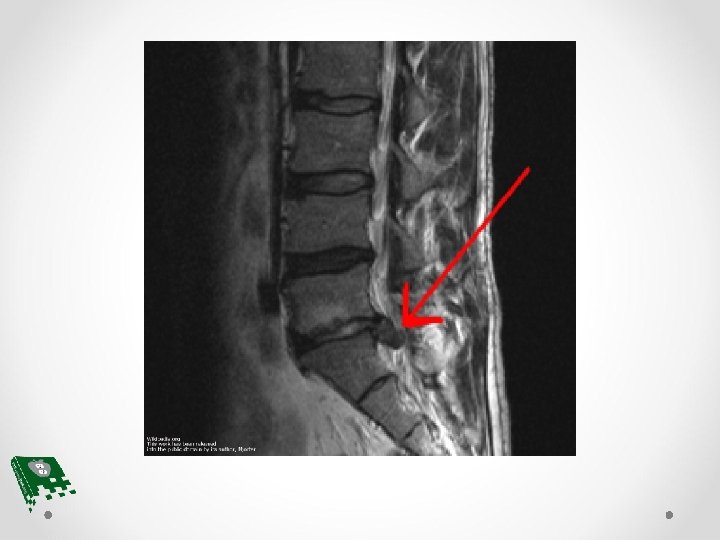

Herniated Disk Mechanism Develops from extruded posterolateral disk fragment or from degeneration of the disk Primary mechanism involves sustained, repetitive cervical loading during contact sports

Herniated Disk Signs and Symptoms • Neck or back pain • Pain may be restricted or diffused • Restriction in neck movement • At some point in the range of motion of the back and neck the herniated disk may become impinged causing extreme pain

Herniated Disk Treatment • Initial treatment involves rest and immobilization of the neck to decrease discomfort • If discomfort is in the lumbar area, rest and an immobilization brace may be helpful • Cervical traction may help reduce symptoms • If this conservative treatment does not help surgical intervention may be necessary